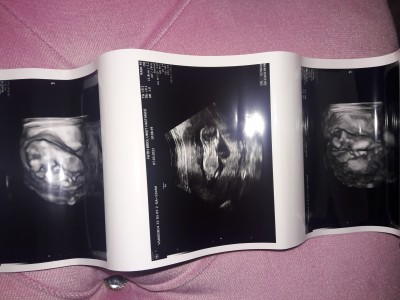

merhaba arkadaşlar 1 ay sonra kontrolüm vardı bugün gittik doktorumuz baktı hiç bi sıkıntı göremedim dedi baş ve boyun poposunu gösterdi kalbini 2. Kez dinledik bu sefer biraz uzun dinleyebildik 6 saniye falan biraz kaçıyodu o yüzden doktor 3 kere dinletti parmaklarini ayaklarını gösterdi cinsiyeti için erken galiba dedim 1 ay sonra söyleyeceğini söyledi bakalım neyim olucak 1 ay sonra büyük gün diyebilirim giderken ikili tarama testi ile gidicem inşallah herşey sağlıklı olur asagidakide ultrason görüntüm

Gebelik haftası 12+4